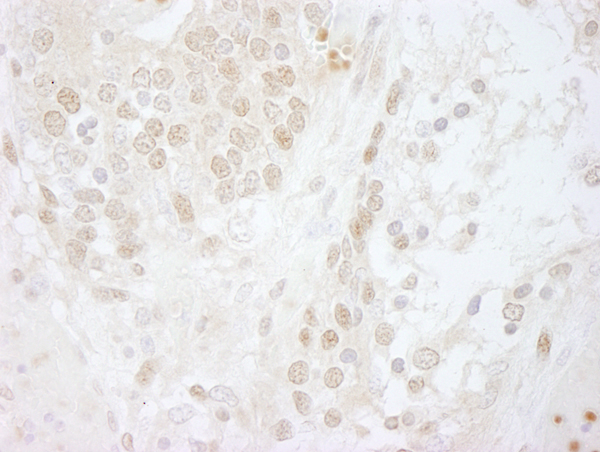

(Detection of human CSN5 by immunohistochemistry. Sample: FFPE section of human islet cell tumor. Antibody: Affinity purified rabbit anti-CSN5 (Cat. No. AAA213976) used at a dilution of 1:250. Detection: DAB)